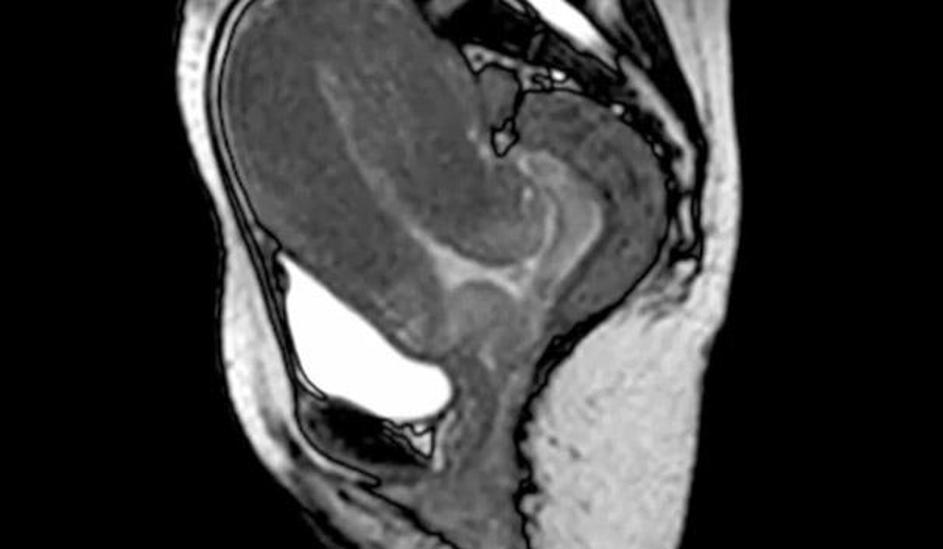

porod, snemanje, magnetna resonanca Poporodni pogled v notranjost maternice brez placente. Žurnal24 porod, snemanje, magnetna resonanca